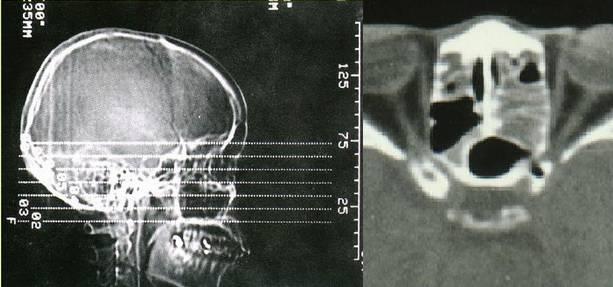

2、影像学检查:CT扫描显示窦口鼻道复合体或鼻窦粘膜病变。

• 副鼻窦X线检查,CT(冠状位、轴位)检查已常规应用。

鼻窦炎冠状CT